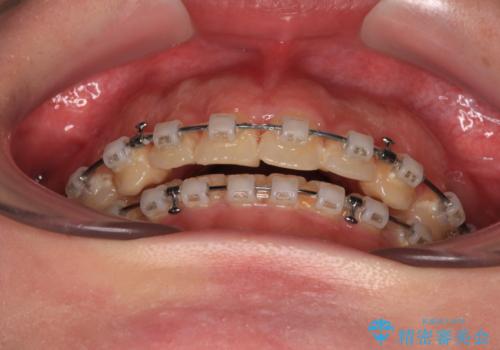

- クリアブラケット

- 3年10ヶ月

ワイヤー矯正でもインビザラインでも対応可能でしたが、上顎歯列が前方位であるときには、ワイヤー矯正の方がより良い仕上がりとなる可能性が高いため、ワイヤー矯正をおすすめいたしました。

舌の突出癖がなかなか改善されず、上下前歯が接触するようになるまでに長期間を要しました。